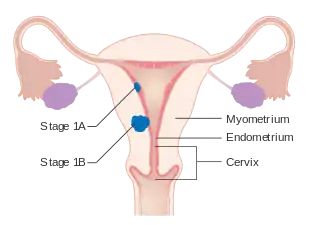

| The location and development of endometrial cancer | |

Staging

Endometrial carcinoma is surgically staged using the FIGO cancer staging system. The 2009 FIGO staging system is as follows:[63][64]

| Stage | Description |

|---|---|

| IA | Tumor is confined to the uterus with less than half myometrial invasion |

| IB | Tumor is confined to the uterus with more than half myometrial invasion |

| II | Tumor involves the uterus and the cervical stroma |

| IIIA | Tumor invades serosa or adnexa |

| IIIB | Vaginal and/or parametrial involvement |

| IIIC1 | Pelvic lymph node involvement |

| IIIC2 | Para-aortic lymph node involvement, with or without pelvic node involvement |

| IVA | Tumor invades bladder mucosa and/or bowel mucosa |

| IVB | Distant metastases including abdominal metastases and/or inguinal lymph nodes |

Myometrial invasion and involvement of the pelvic and para-aortic lymph nodes are the most commonly seen patterns of spread.[2] A Stage 0 is sometimes included, in this case it is referred to as "carcinoma in situ".[9] In 26% of presumably early-stage cancers, intraoperative staging revealed pelvic and distant metastases, making comprehensive surgical staging necessary.[27]

Stage IA and IB endometrial cancer

Stage IA and IB endometrial cancer Stage II endometrial cancer

Stage II endometrial cancer Stage III endometrial cancer

Stage III endometrial cancer Stage IV endometrial cancer

Stage IV endometrial cancer